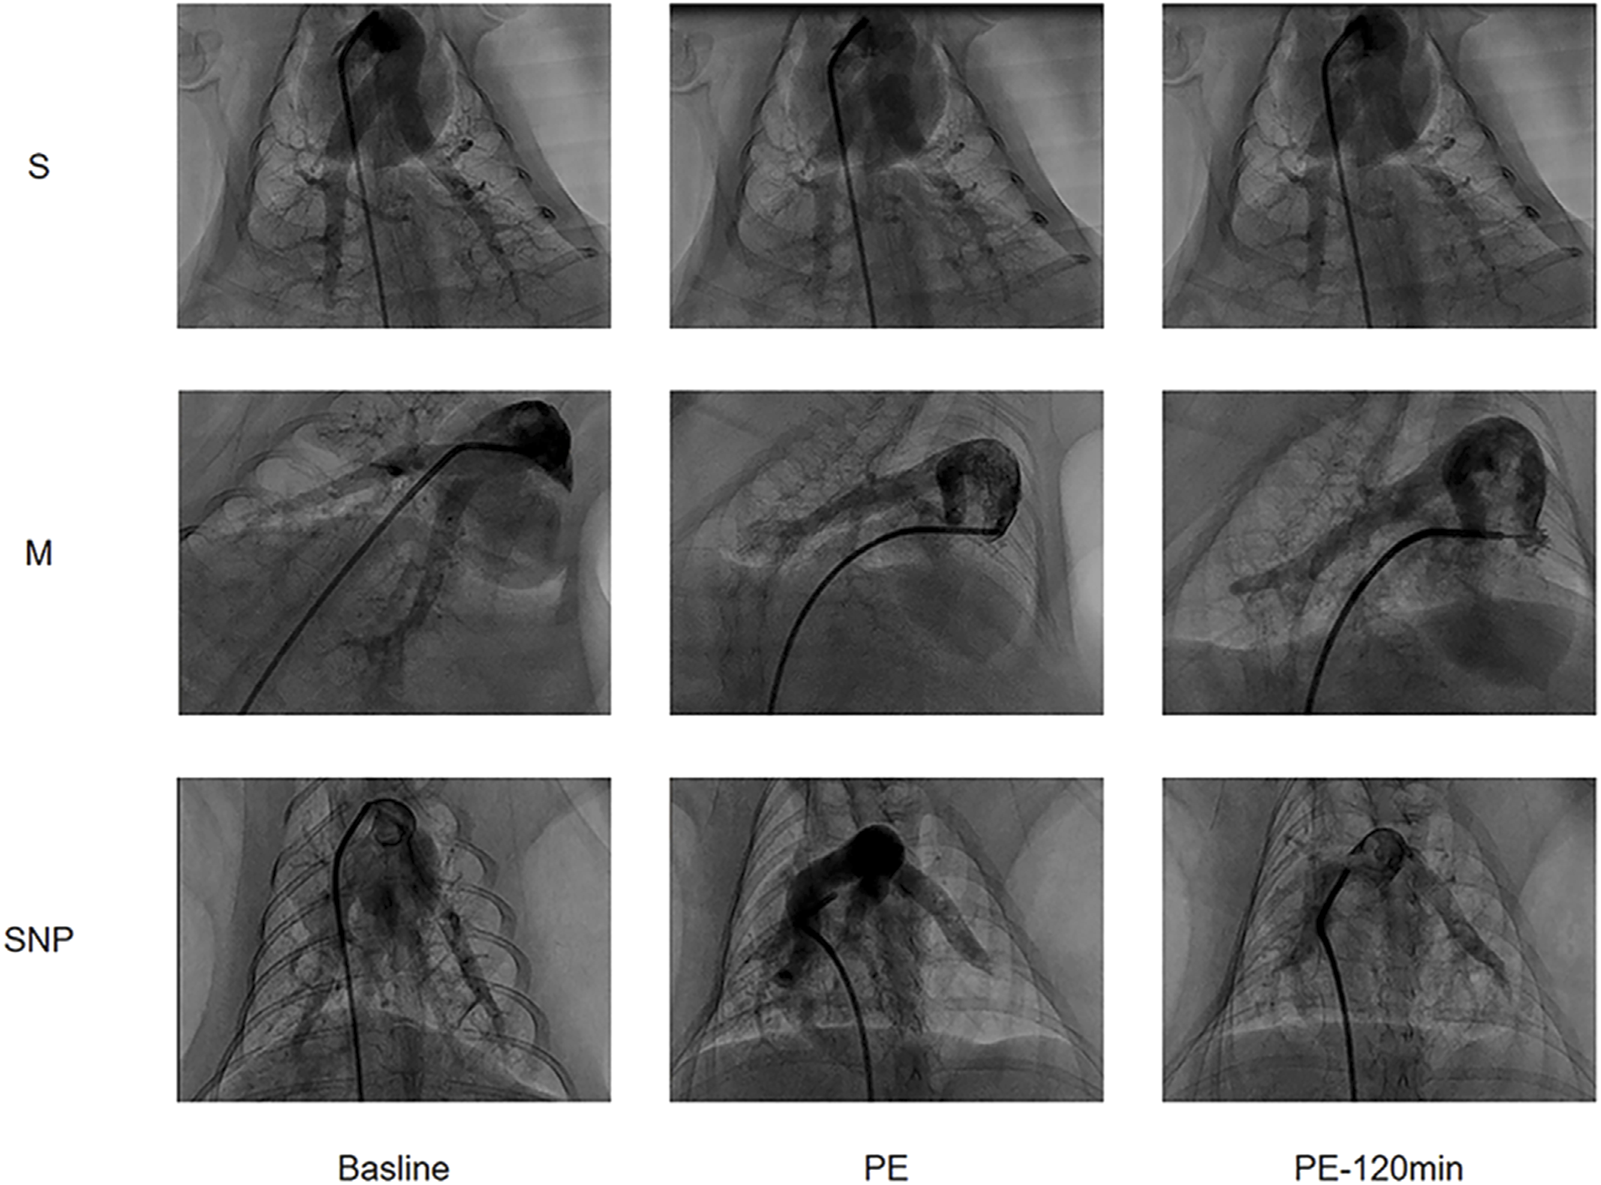

Pulmonary angiography

Pulmonary angiography images were obtained at baseline, at the moment of successful modeling, and at 120 min after the successful modelling (Figure 2). The blood flow conditions in each group were similar at baseline, reduced in M and SNP groups and was significantly improved at 120 min in SNP group as compared to M group.

Figure 2. Pulmonary Angiography images arranged in a 3x3 grid showing three different labels (S, M, SNP) across three time points (Baseline, PE, PE-120 min). Each row represents a different condition (S, M, SNP) and each column shows the progression over time. The images display contrast-filled blood vessels or structures, with visible changes of Pulmonary Embolism.